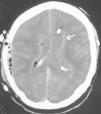

Ingresó en un hospital comarcal por presentar cuadro de fiebre, cefalea, náuseas y vómitos de 48 horas de evolución. Se realizó tomografía axial computarizada (TAC) craneal sin contraste (fig. 1), apreciándose lesión temporoparietal derecha de 2,8 x 2,6 cm compatible con absceso cerebral.

Figura 1. Lesión hipodensa temporoparietal derecha.